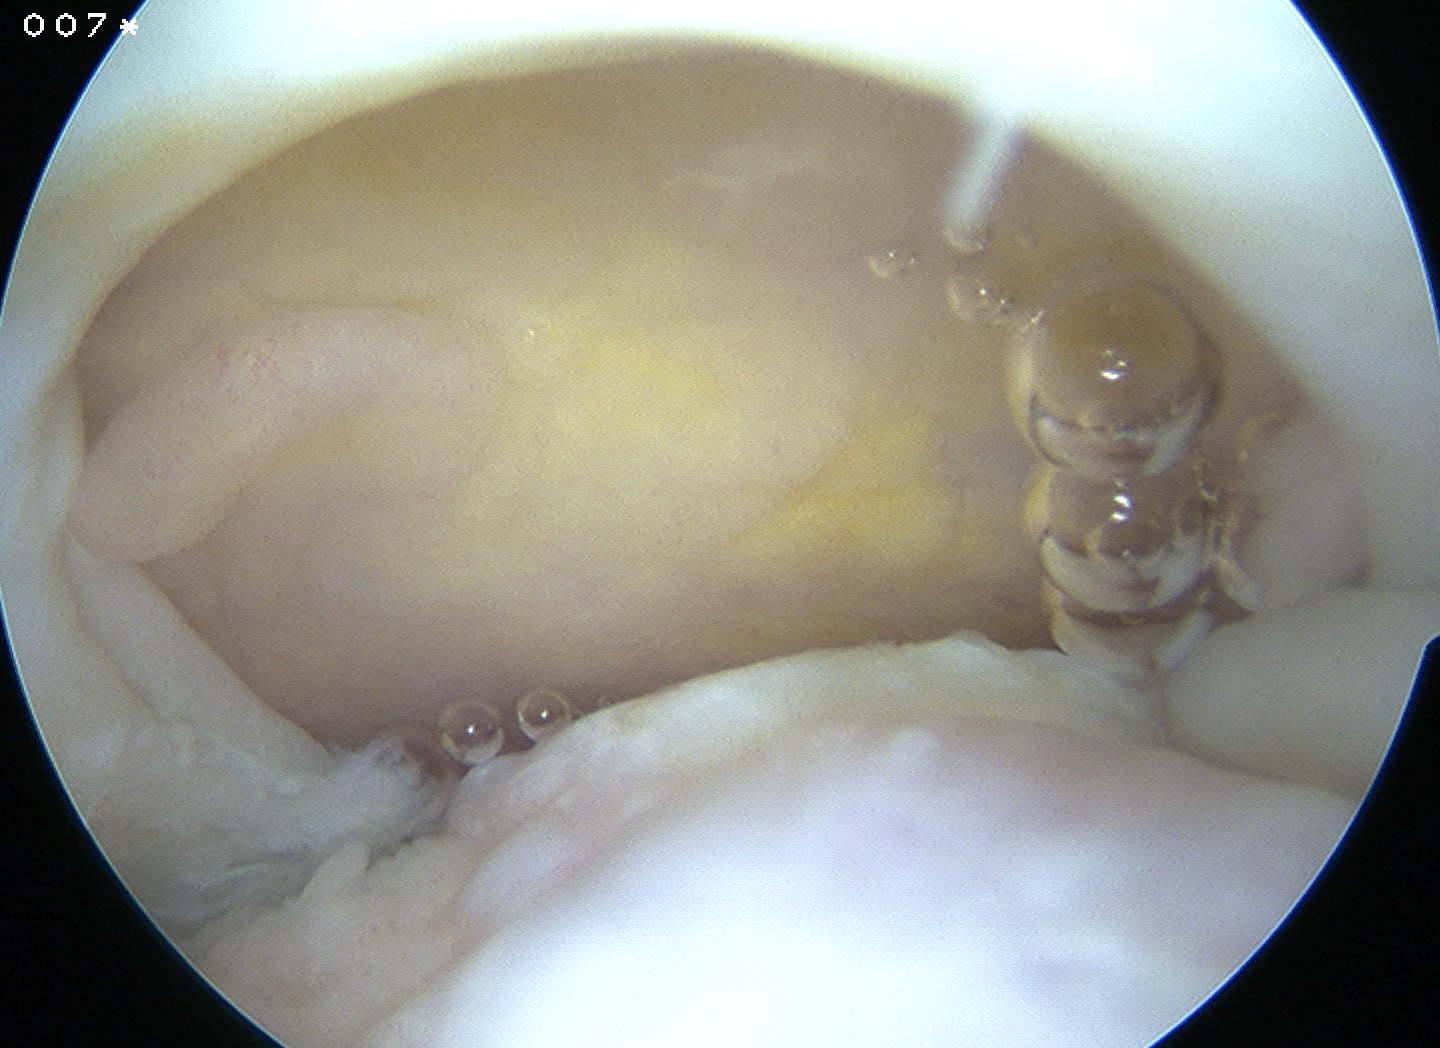

PVNS

Definition

Pigmented Villo-Nodular Synovitis

- benign inflammatory process that arises in synovial tissues

- contains significant amounts of hemosiderin

A. Diffuse

- throughout joint synovium

- more difficult to treat / excise fully